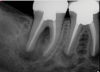

(3.) Preoperative radiograph of asymptomatic carious exposures on teeth Nos. 12 and 13.

Figure 3

(4.) Postoperative radiograph of teeth Nos. 12 and 13 following treatment with direct pulp caps using a bioceramic dentin substitute material.

Figure 4